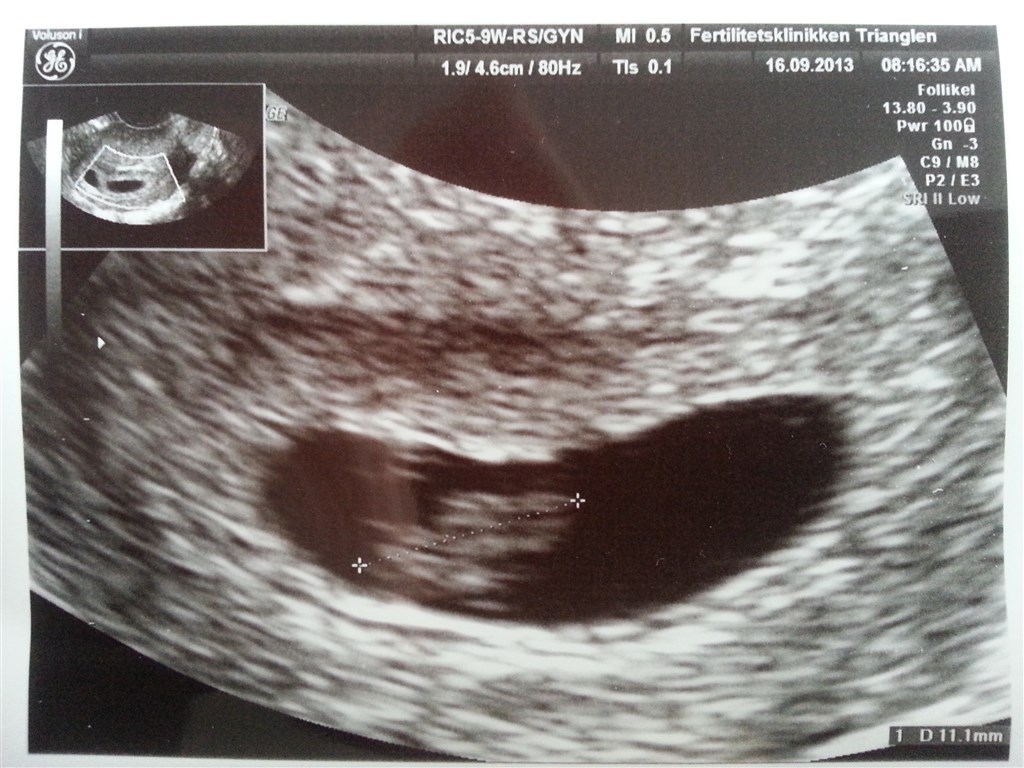

Det var en kæmpe lettelse at se, at hjertet banker derudaf. Lægen var også meget fortrøstningsfuld om, at den ville blive.

Jeg har det faktisk fint med den tomme blommesæk, så længe der er 1 levende foster.. Men min mand blev desværre ret nervøs af det. Han er bange for at det betyder at det andet også går i stå.

Det er bare noget af det største at se der rent faktisk er en lille prik der slår derinde.